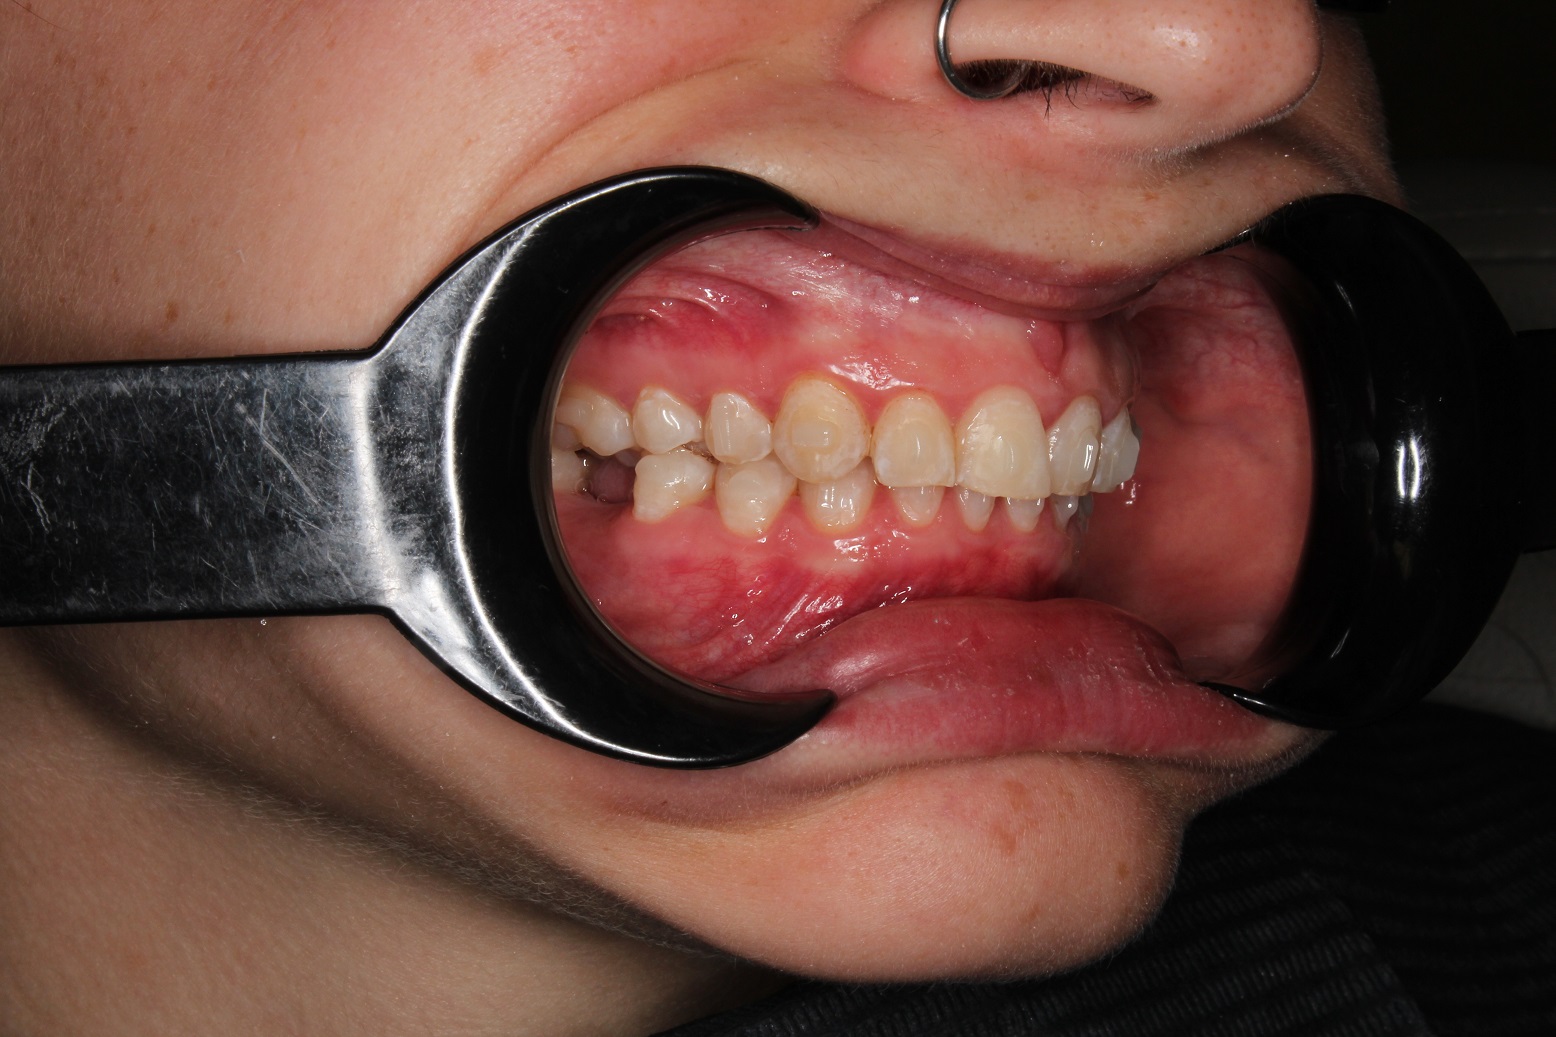

До и После: Лечение глубокого прикуса элайнерами

Лечение глубокого прикуса элайнерами. Начало лечения. Фиксация элайнеров